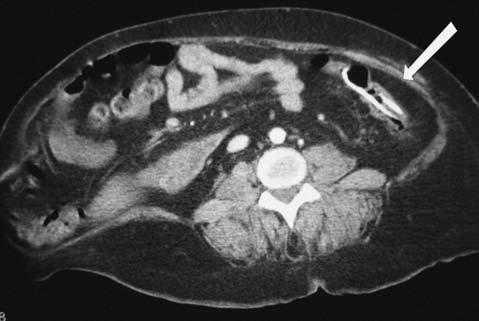

Presentamos el caso de una paciente de 39 años, portadora de una válvula de derivación ventriculoperitoneal por una hidrocefalia normotensiva, que presentó un cuadro de dolor abdominal progresivo, de 24 horas de evolución. La paciente refería cefalea y, en la exploración, presentaba dolor en el hipocondrio y el flanco izquierdo. La analítica evidenció leucocitosis con desviación izquierda. Una tomografía computarizada mostró el catéter situado en la luz del colon, así como peritonitis local con infiltración de la grasa pericolónica (figs. 1 y 2). Se instauró tratamiento antibiótico de amplio espectro y se decidió retirar el catéter de derivación ventriculoperitoneal, y colocar un drenaje externo. La paciente evolucionó satisfactoriamente, y se reimplantó una nueva válvula y un catéter de derivación ventriculoperitoneal.

Fig. 1. Imagen de tomografía computarizada donde se visualiza catéter intraluminal con infiltración de grasa pericolónica.